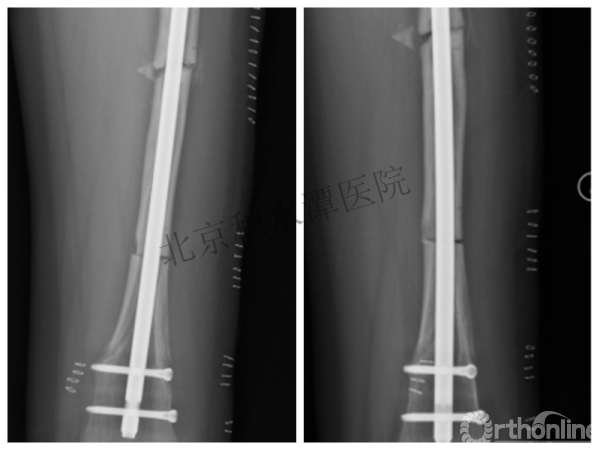

病例分享一

男孩 、5岁,初次骨折于2007年7月。

术后2年→再骨折→再次手术

钢板固定后一年

取板后再骨折→TEN

TEN取出后2个月

闭合复位再固定加尾帽

又过了4年!时间来到2015年